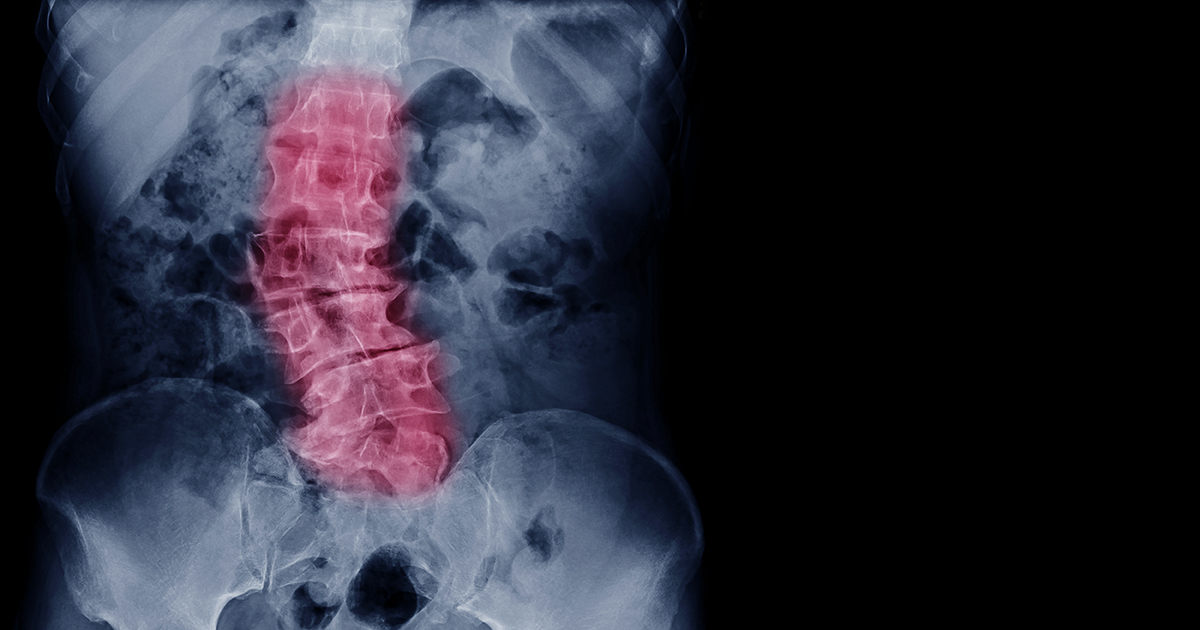

Scoliosis is one of the most common types of spinal deformity. It’s an abnormal curvature of the spine either front-to-back or side-to-side. Although it sounds scary, a scoliosis diagnosis is not a guaranteed ticket to the operating room for spinal surgery. There are multiple types of scoliosis and a wide range in how they affect people.

For some, scoliosis won’t progress beyond a slight painless curve of the spine, and it won’t ever progress. For others, scoliosis can become so extreme it interferes with lung capacity, or causes extreme pain in the back or legs. Each scoliosis case is unique, so there is no one-size-fits-all treatment.